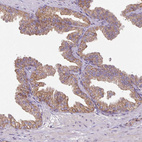

Immunohistochemical staining of human rectum shows moderate granular cytoplasmic positivity in glandular cells.